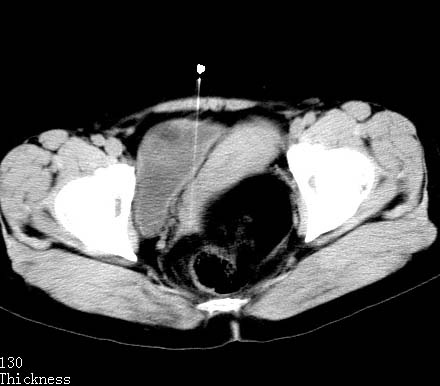

女性 病人 44岁 盆腔 下腹部痛1天!

盆腔多发畸胎瘤

盆腔内低密度为主混杂等密度及少许囊样与班状钙化影,如果做了肠道准备就好了。支持畸胎瘤。当然做mri会更好

典型的双侧附件畸胎瘤.